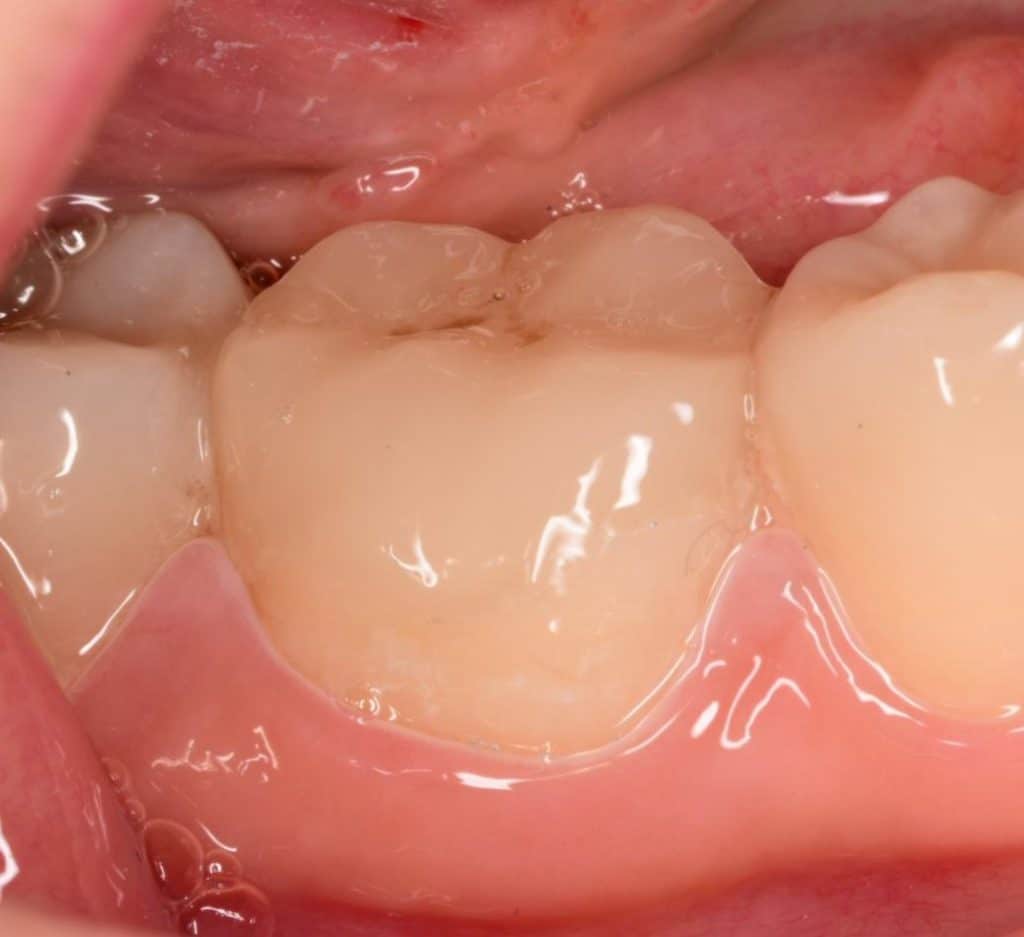

Initial situation showing large defective composite filling

During Old composite removal you can see the liner this type of liner have weak adhesion to dentin and so post operative sensitivity will occur, the best liner under composite is the bond itself

You can see the liner below the old composite ,irregular margins, mesial wall of the second molar need to be restored

Here you can see that the remaining walls are weak and must reduced and replaced by strong indirect lithium disilicate overlay